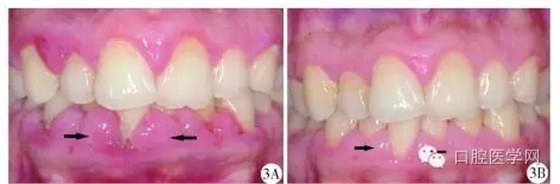

2013年1月,患者因前牙區(qū)牙齦腫脹伴刷牙出血就診于北京協(xié)和醫(yī)院口腔科,行下前牙區(qū)牙齦組織活檢,切片示上皮下炎癥性的纖維組織增生,血涂片檢查未見確切異常,行洗牙治療后自覺牙齦腫脹緩解不明顯,1個月后就診于北京大學(xué)口腔醫(yī)院牙周科,口內(nèi)檢查發(fā)現(xiàn)全口牙齦乳頭普遍紅腫增生,質(zhì)地韌,上、下前牙區(qū)尤為明顯(圖3A)。牙周探診深度(probing depth,PD)普遍4~7mm,中等量菌斑,探及大量齦下牙石,探診出血74.0%。全口根尖片顯示普遍的牙槽骨輕度吸收(圖4)。

基礎(chǔ)治療后6周復(fù)查時患者的牙齦色、形、質(zhì)與口腔衛(wèi)生情況都有了極大改善(圖3B),牙周檢查表顯示治療前后患者每顆牙的平均PD變化(圖6),探診出血也由74.0%下降到33.3%。